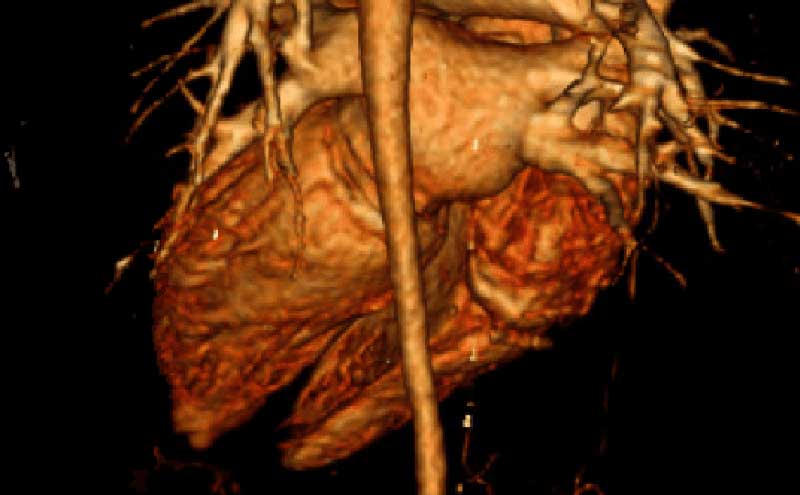

Patient underwent CT angiogram of her chest and abdomen emergently and the findings were suspicious for “periaortitis in association with midaortic syndrome with severe stenosis/near occlusion of the infrarenal aorta, bilateral renal arteries, celiac trunk, and SMA.” Findings that could represent a vasculitis versus neoplastic process.

Narrowing of aorta recon